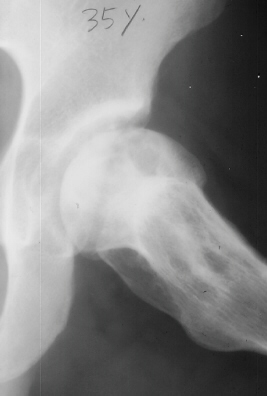

At 28 years of age, he had been having increasing pain in his right hip. He had a limp when he was tired. Positive Trendelenburg's sign was observed on the right. Internal rotation was limited to 25 degrees. All other motions were normal. X-ray showed cystic change. At the 29 years of age, he underwent bone graft of the right femoral head for degenerative cyst. At 35 years of age, only internal rotation was limited to 20 degrees. He still had pain in his hip that relates primarily to weather or to excessive walking. Only internal rotation was limited to 20 degrees. He had hip pain at the extremes of flexion and internal rotation. X-ray showed the progression of the cystic change. CT which was performed because of the question of loose bodies in the hip did not seem likely that the densities were actually in the hip joint. The antero-medial location of the cysts facing the anterior margin of the acetabulum was well depicted in CT.